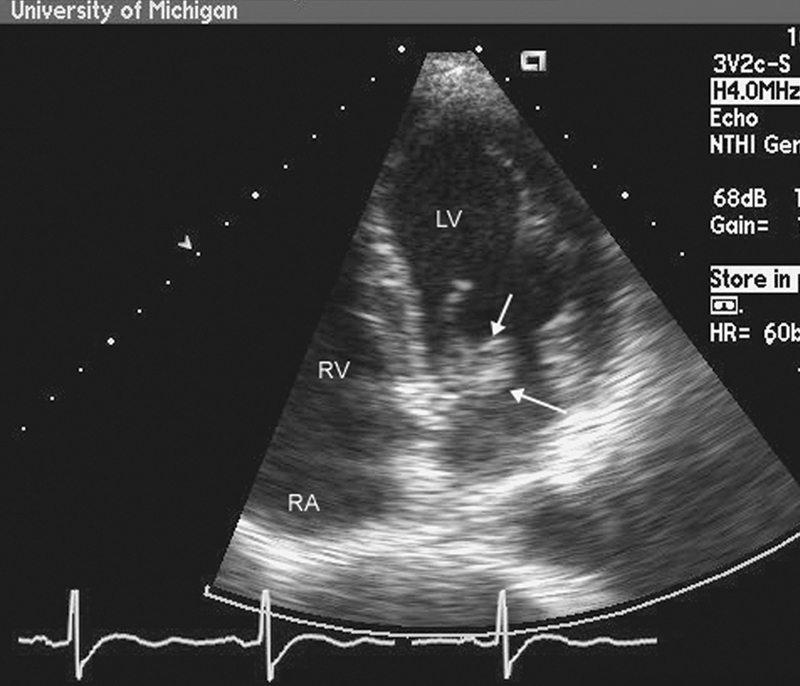

فحوصات تشخيصية لبعض امراض القلب والشرايين التاجية